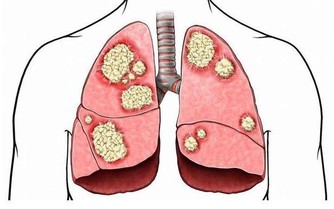

1、如果你的疼痛一直擺脫不了,去看看醫生

有時候落枕是大問題的症狀,和椎間盤突出或神經受壓差不多。

這種傷害可能自己康復不了,要求醫來確認自己是否需要醫治。

如果坐起、站立、走路有困難、疼痛不消失,或者要好幾天才能好,諮詢一下醫生,

看看你是否有嚴重的頸部受傷